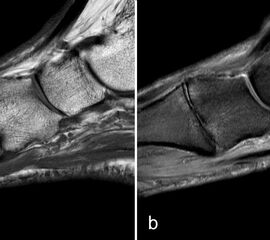

Rupturen ereignen sich am häufigsten an den distalen Insertionen der Metatarsophalan­gealgelenke (Abb. 5), etwas seltener auf Höhe der Metatarsaleköpfchen. Die Läsionen können sehr umschrieben sein, quer durch die gesamte plantare Platte reichen und sich sogar bis in die Kollateralbänder fortsetzen 1. Rupturen der plantaren Platte finden sich am häufigsten an der zweiten Zehe, die dritte Zehe ist etwas seltener betroffen. An der vierten und fünften Zehe sind die Läsionen sehr ungewöhnlich. Rupturen der pantaren Platte führen häufig zu einer ausgeprägten Weichteilreaktion, die nicht als Morton-Neurom fehlgedeutet werden sollte (Abb. 6) und zur Ausbildung einer Neo-Bursa führen können (Abb. 7).

Die sagittalen PD FS Schichten im medialen und lateralen Bereich der plantaren Platte (a, c) zeigen eine völlig unauffällige,  Der kleine Flüssigkeitseinschluss in der Mittellinie der Zehe (b, Pfeil) entspricht einem physiolo

Abbildung 9

Zwischen der plantaren Platte und der Grundphalanx ist in der Mittellinie des Gelenkes ein kleiner Rezessus vorhanden (Abb. 9).

Dieser flüssigkeitsgefüllte Raum darf nicht als Ruptur der plantaren Platte fehlinterpretiert werden 23. Verletzungen der plantaren Platte erfassen immer auch den medialen oder lateralen Zügel.